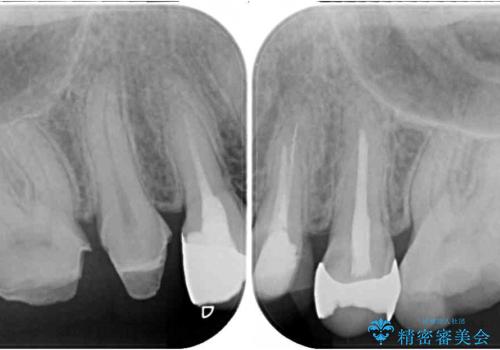

- 奥歯を治療しようと他院で開始したものの、放置してしまったとのことで来院された患者様です。

外れてしまった銀歯や穴の空いた仮歯などあり、適合の悪い被せものと合わせて、セラミッククラウンやセラミックインレーにて治療と行うこととしました。